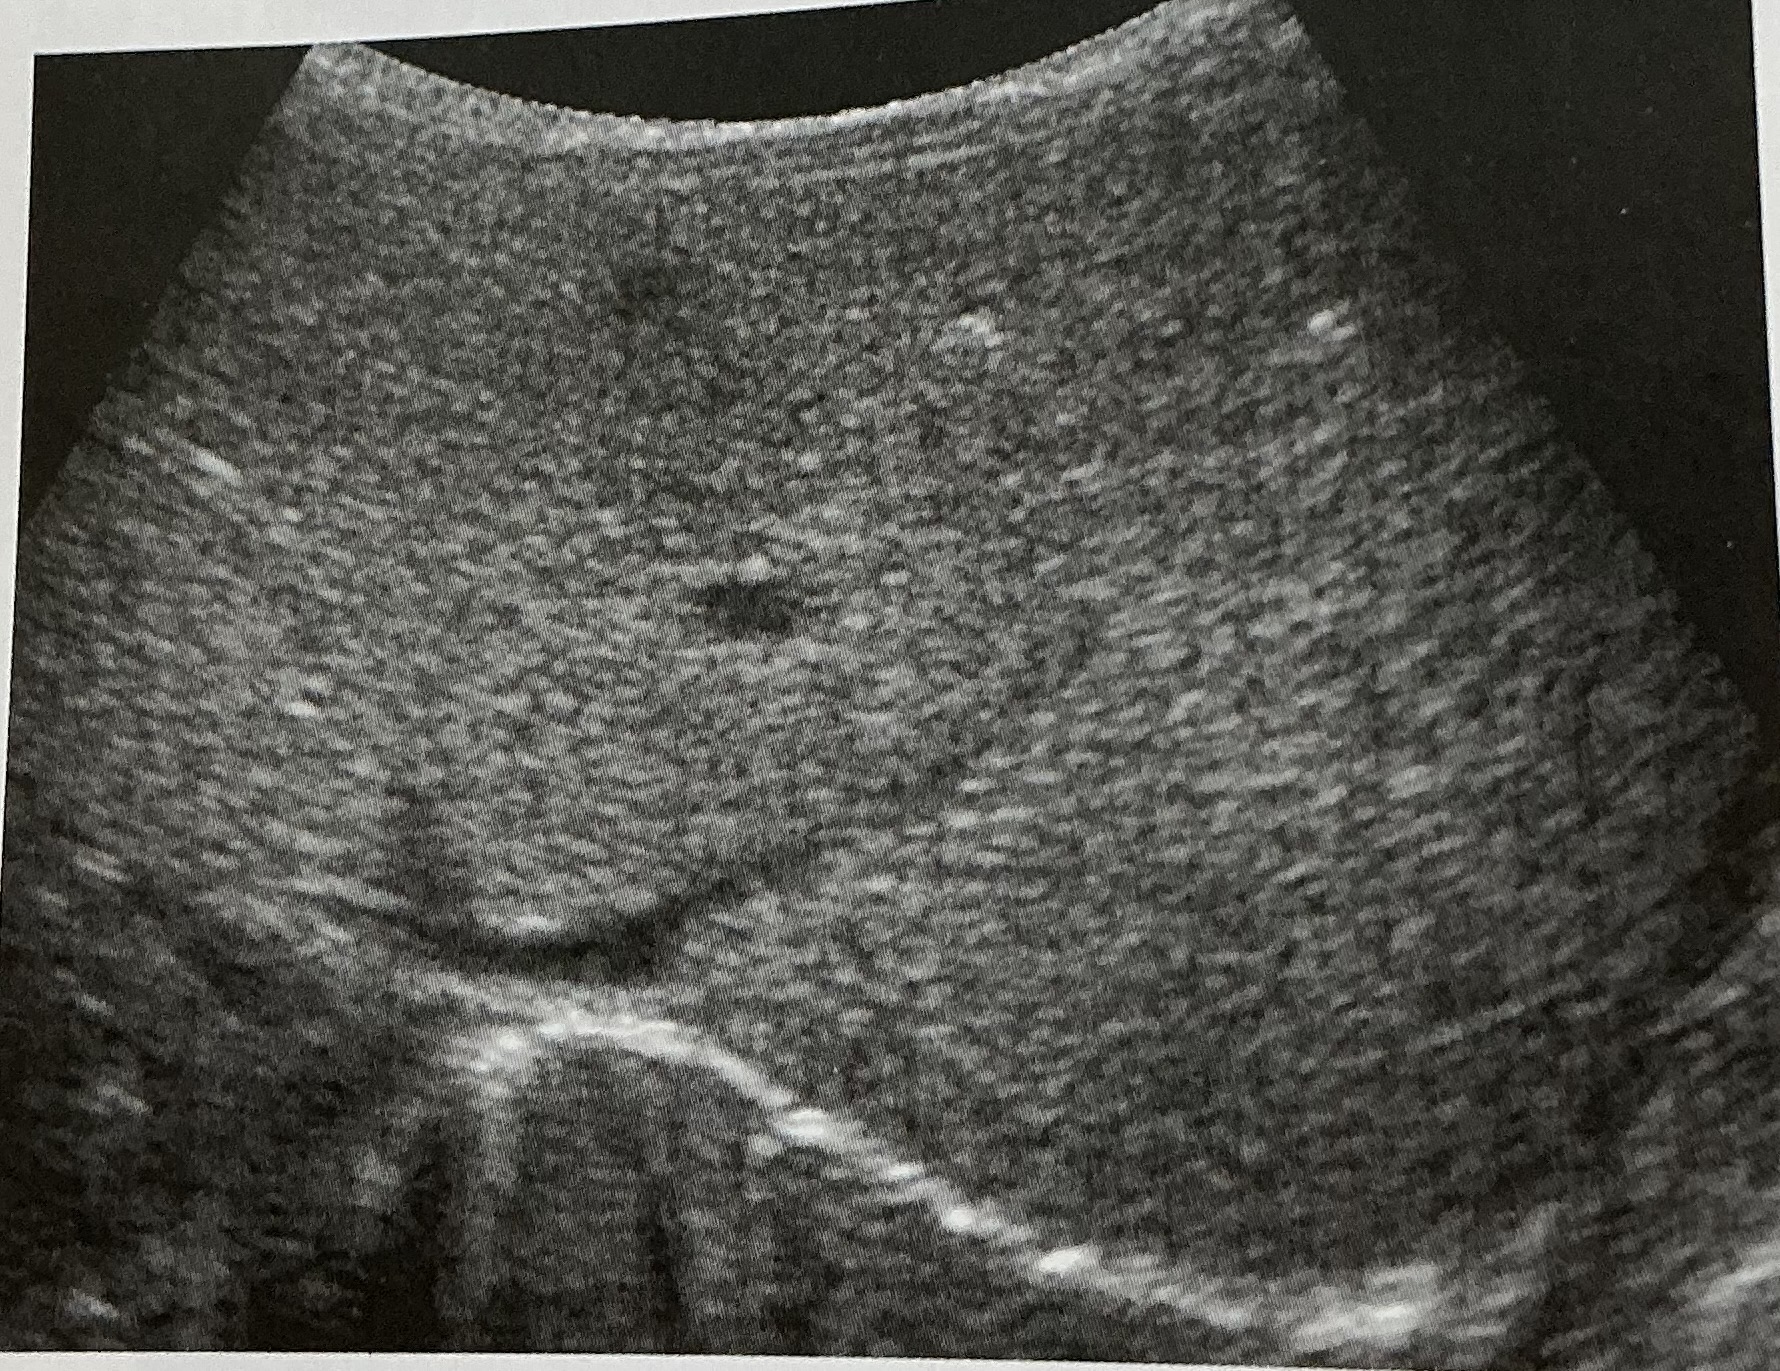

Label this image